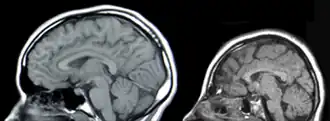

La microcéphalie concerne toutes les formes de croissance anormalement faible de la boîte crânienne et du cerveau. Elle se manifeste par des mesures crâniennes : périmètre et diamètre de la tête, inférieurs à la normale.

Les nourrissons atteints de microcéphalie naissent avec une tête de taille réduite, ou de taille normale, mais dont le crâne ne grandira pas normalement alors que la face continue à se développer à un rythme normal, formant un front fuyant, et un cuir chevelu distendu et souvent ridé. Au fur et à mesure de la croissance de l'enfant, la petitesse du crâne devient plus évidente, mais tout le corps est souvent aussi concerné par un retard de croissance. Selon les cas, les fonctions motrices sont plus ou moins affectées (jusqu'à une quadriplégie spastique parfois). De même pour l'acquisition de la parole, qui est plus ou moins retardée. Une hyperactivité et une déficience intellectuelle sont courantes, mais plus ou moins marquées selon les cas. Des convulsions peuvent survenir.